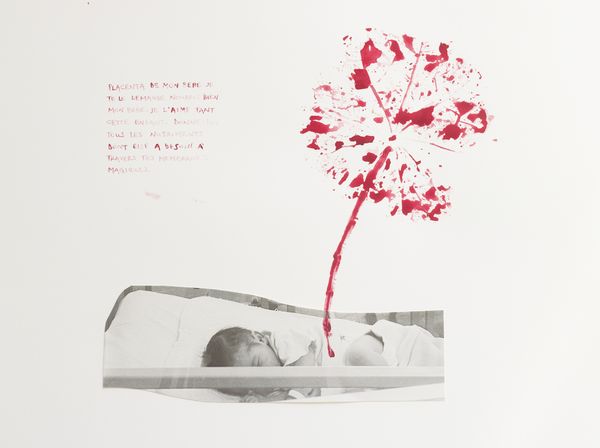

ALPHA PROJECT BY PAMELA PISCICELLI AND JULIETTE WAYENBERG

They tell you that they will take your baby away to the nursery, because you are not able to take care of her right now.

You don’t understand.

Why can't your baby stay with you?

They take her away.

They tell you that if you are well enough you can go see your baby at the nursery in the morning.

You have just given birth, and you have to ask permission to see your baby.

You arrive at the nursery: a few square feet of functional space.

Too many neons. Too much noise. Too much heat. Eighteen plastic boxes, they call them "cradles". Inside these boxes, eighteen screaming newborns. What can these babies do, for endless hours, but scream at the top of their lungs. They need everything, not this cold reality.

The medicalization of birth, the result of a sanitary, paternalistic and patriarchal mindset, has transformed the most primitive and intuitive moment into an event to be dealt with. Women full of oxytocin are sedated and tempered, in the name of a supreme wellness they themselves ignore. Defenseless babies are manipulated and immediately taken away so as not to disturb the professionals. They are placed in the care of paid strangers, covered in latex in a cold room called the 'nursery'. The procedural system kicks in. Patriarchy takes revenge.

What do newborn babies see? How do they feel? What kind of stress do they experience in the unnatural transition from womb to hospitalization? What trauma do they retain of their first experience of abandonment? What would it be like to take the side of babies for once, listen to them and interpret their needs ignored by a society designed for adults?

Alpha is urgent. It is the search for primordial unity, that of the mother-child dyad. Alpha is the first letter, the first time, the first deprivation. It is also, from a neurological point of view, a slightly altered state of consciousness, that of dreams and children.

At first, an adult-sized plexiglass box reproducing a cradle immerses the audience in a nursery space where, surrounded by artworks hanging from the ceiling and placed on the floor, they will experience the harsh reality, without liquid, without a mother of a hospital maternity. Then, guided by the sound of the heartbeat as heard from inside the womb, and through visual installations and video dance panels, they will be brought back to the gestational age, highlighting the clash with the outside world.

Alpha is a denunciation and cathartic. Through images, words and sounds, it embodies the first emotional traumas and the violence inherent in zero-risk policy lead societies that seek efficiency, at the cost of losing our humanity.